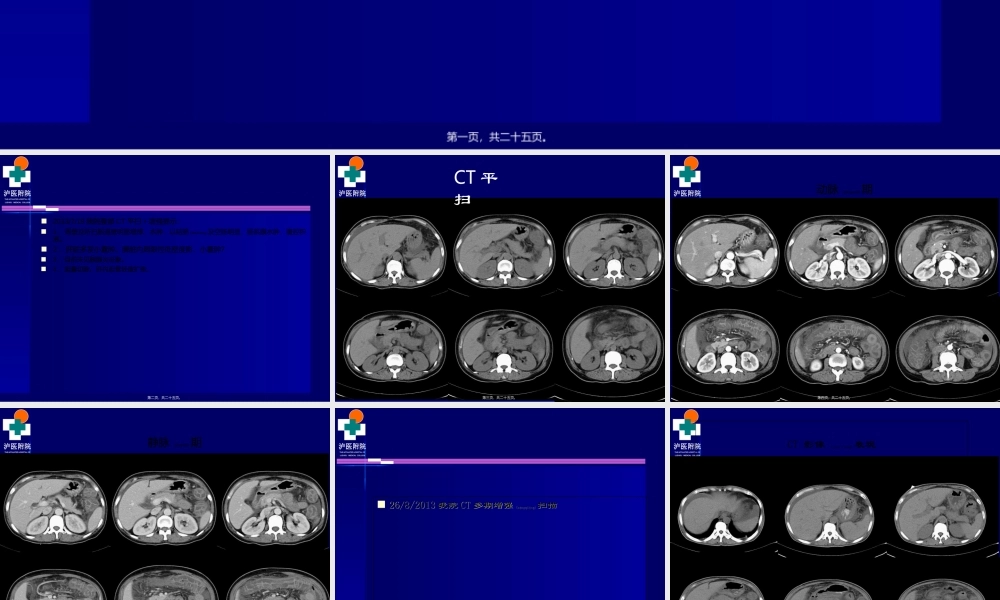

泸医附院THEAFFILIATEDHOSPITALOFLUZHOUMEDICALCOLLEGE院外电解质K+2.06mmol/L胃镜提示:慢性非萎缩性胃炎(wèiyán)伴胆汁反流,胃潴留,动脉血气分析K+<2.0mmol/L,BE-8mmol/L第一页,共二十五页。泸医附院THEAFFILIATEDHOSPITALOFLUZHOUMEDICALCOLLEGE2013/7/19我院腹部CT平扫+增强提示:1、胃壁及所扫肠道壁明显增厚、水肿,以结肠(jiécháng)及空肠明显,肠系膜水肿,腹腔积液。2、肝脏多发小囊肿。脾脏内局限性低密度影,小囊肿?3、目前未见胰腺炎征象。4、胆囊切除。肝内胆管轻度扩张。第二页,共二十五页。泸医附院THEAFFILIATEDHOSPITALOFLUZHOUMEDICALCOLLEGECT平扫第三页,共二十五页。泸医附院THEAFFILIATEDHOSPITALOFLUZHOUMEDICALCOLLEGE动脉(dòngmài)期第四页,共二十五页。泸医附院THEAFFILIATEDHOSPITALOFLUZHOUMEDICALCOLLEGE静脉(jìngmài)期第五页,共二十五页。泸医附院THEAFFILIATEDHOSPITALOFLUZHOUMEDICALCOLLEGE2626//8/20138/2013我院我院CTCT多期增强多期增强(zēngqiáng)(zēngqiáng)扫描扫描第六页,共二十五页。泸医附院THEAFFILIATEDHOSPITALOFLUZHOUMEDICALCOLLEGECT影像(yǐnɡxiànɡ)表现第七页,共二十五页。泸医附院THEAFFILIATEDHOSPITALOFLUZHOUMEDICALCOLLEGE第八页,共二十五页。泸医附院THEAFFILIATEDHOSPITALOFLUZHOUMEDICALCOLLEGE第九页,共二十五页。泸医附院THEAFFILIATEDHOSPITALOFLUZHOUMEDICALCOLLEGE第十页,共二十五页。泸医附院THEAFFILIATEDHOSPITALOFLUZHOUMEDICALCOLLEGE第十一页,共二十五页。泸医附院THEAFFILIATEDHOSPITALOFLUZHOUMEDICALCOLLEGE第十二页,共二十五页。泸医附院THEAFFILIATEDHOSPITALOFLUZHOUMEDICALCOLLEGE第十三页,共二十五页。泸医附院THEAFFILIATEDHOSPITALOFLUZHOUMEDICALCOLLEGE第十四页,共二十五页。泸医附院THEAFFILIATEDHOSPITALOFLUZHOUMEDICALCOLLEGE诊断诊断(zhěnduàn)(zhěnduàn)结果??结果??第十五页,共二十五页。泸医附院THEAFFILIATEDHOSPITALOFLUZHOUMEDICALCOLLEGE肝脏形态大小未见异常,边缘光整,其内密度欠均匀,肝左叶见两枚类圆形低密度影,大者约肝脏形态大小未见异常,边缘光整,其内密度欠均匀,肝左叶见两枚类圆形低密度影,大者约0.6cm0.6cm位于左外叶,无强化。肝内胆管稍扩位于左外叶,无强化。肝内胆管稍扩张,其内未见高密度结石影。胆囊未见显示。脾脏形态大小尚可,脾脏前份见小圆形低密度影,...